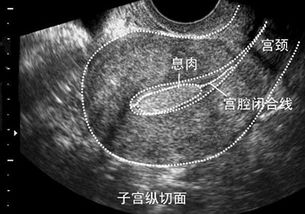

7、這兩種息肉癌變的幾率大嗎?我挺害怕的,病理結果要過兩天才出。

不大,拘報告是不到5%

病情分析: 你好,子宮內膜息肉刮宮手術后該注意刮宮術后一定要預防感染治療,飲食上禁食生冷,辛辣刺激性食物,不要過度勞累. 多吃點富含營養(yǎng)的食物,因為有貧血可以適當?shù)暮赛c豬肝湯補補血.你的子宮內膜息肉建議做切除術 食補可以有:豬肝湯,桂圓蓮子湯,羊骨湯,阿膠等等.對于您問的手術后飲食上注意什么,手術后最好不要吃生蒜,辣椒,麻椒,鰻魚,咸魚,羊肉,蝦,蟹等,還要忌食生蔥,白酒等刺激性食物及飲料.另外有什么異常情況應及時隨訪.以上就是我的回答,希望您可以滿意.。